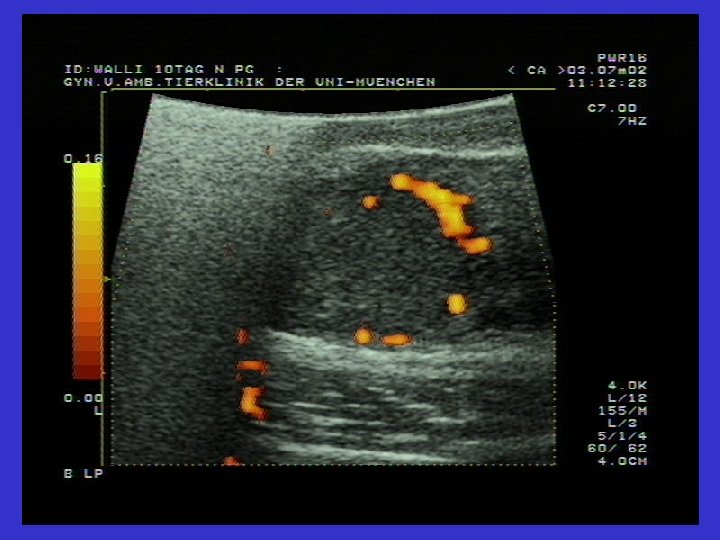

Graaf follikülü ve Follikül Theka kistlerinin karşılaştırmalı ultrasonografik görüntüsü

Follikül lutein kistlerinin tanısı • • Follikül 2, 5 cm den büyüktür Anöstrus gözlenir Persistenz (=kalıcıdır); genellikle soliterdir Ultrasonografi: ortada anekojen; çevresi hipoekojen (gri) (>3 mm) • P 4= serum (1 ng/ml=3, 18 nmol/L) süt= 10 ng/ml den yüksek (Aslan, 2000) • Uterus yangısı ile birlikte görülebilirler (Arbeiter ve ark. , 1991; Zerbe ve ark. , 1999)

Ovaryum luteal kistlerinin ultrasonografik görüntüsü Solda ovaryum luteal kisti (31 mm). Gri Hipoekojenik alan çepeçevre seçiliyor.